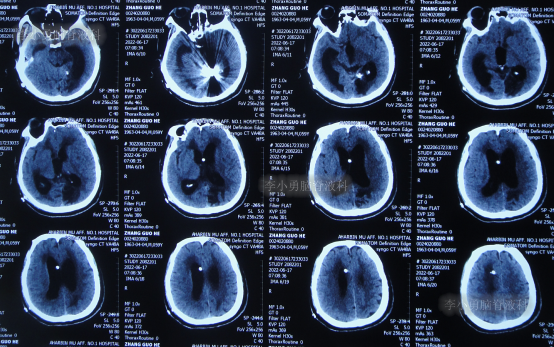

2022年4月27日(入院治疗3天),脑脊液培养出细菌,给予抗感染治疗,查头颅CT示脑室扩张加重(图-5)。

图-5:2022年4月27日头颅CT

抗感染治疗28天即2022年5月25日,查头颅CT示仍脑积水(图-6),脑脊液仍有细菌。

图-6:2022年5月25日头颅CT

抗感染治疗41天即2022年6月7日,脑脊液化验细菌消失,但查头颅CT示仍脑积水(图-7)。

图-7:2022年6月7日头颅CT